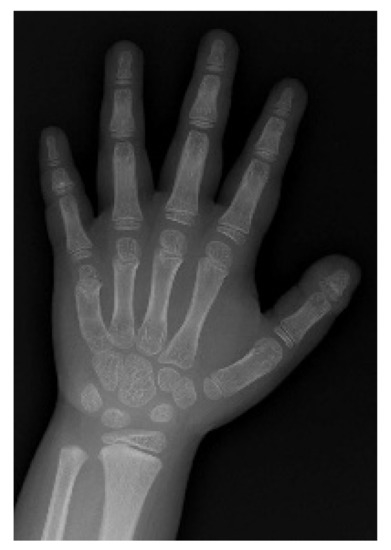

| Thyroid Function (Units) (Reference Range) | Ventriculomegaly | Bladder Stone | GDPP |

|---|---|---|---|

| T3 (ng/mL) (0.94–2.41) | 4.00 | 1.58 | 1.93 |

| fT4 (ng/dL) (0.80–2.00) | 3.76 | 1.40 | 0.94 |

| TSH (mIU/L) (0.60–8.00) | 0.06 | 0.09 | 0.01 |